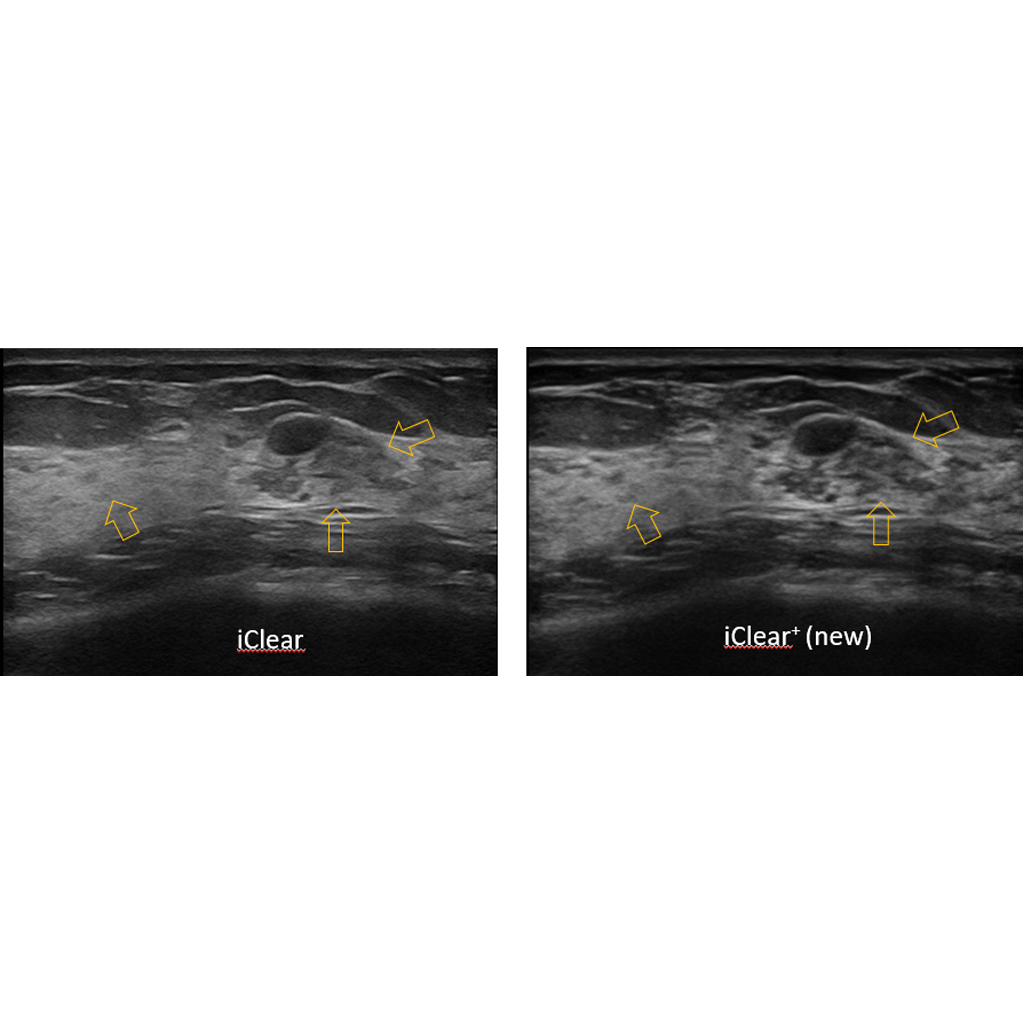

Система за адаптивно потискане на зърнистите артефакти (speckle suppression) – иновативна технология с настройка на няколко степени, която:

- намалява шума / отблясъците и така значително подобрява тъканната диференциация

- подобрява дефинирането на границите и увеличава диагностичната акуратност

- подобрява контрастната резолюция, запазвайки отлична пространствена резолюция.

iClear + е последна генерация разширена версия на iClear с допълнително подобрение на качество на изображението, изчистване на шума, осигуряване на по-добър контраст и разделителна способност, и по-лесно идентифициране на лезии